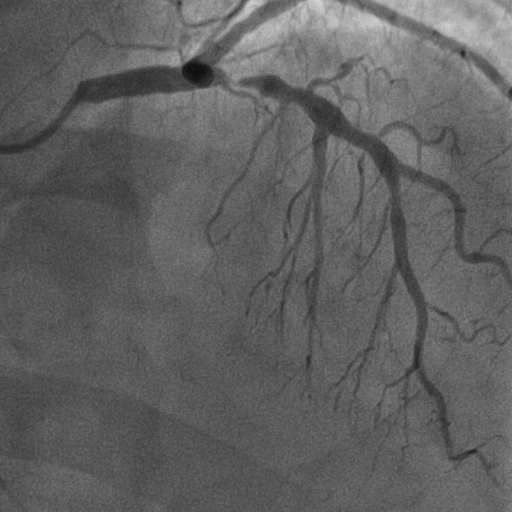

การตรวจประเมินหลอดเลือดหัวใจชนิดไม่รุกราน (Non Invasive) ได้รับความนิยมเพิ่มขึ้น ทั้งการทำ Stress Echocardiography, Stress Cardiac Magnetic Resonance Imaging (Stress MRI) และ Coronary Computed Tomographic Angiography (CCTA) ซึ่งสามารถคัดกรองผู้ป่วยที่มีผลการตรวจปกติหรือผิดปกติเพียงเล็กน้อยออกไป โดยไม่จำเป็นต้องไปถึง การฉีดสีสวนหัวใจ (Coronary Angiography: CAG) ซึ่งเป็นการตรวจชนิดรุกราน (Invasive) และมีภาวะแทรกซ้อนมากกว่า แต่ในกรณีที่ผลการตรวจผิดปกติชัดเจนมักจะนำไปสู่การฉีดสีสวนหัวใจ ซึ่งเป็นมาตรฐานในการวินิจฉัยโรคหลอดเลือดหัวใจ

ภาพการฉีดสีสวนหัวใจ (Coronary Angiography : CAG)